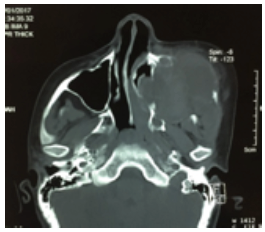

Paciente femenina de 8 años de edad, recibida en el mes de octubre de 2016, asintomática, sin antecedentes patológicos, alérgicos y quirúrgicos. Intraoralmente, presenta una masa tumoral de aproximadamente 6 x 6 cm a expensas de maxilar, que desplaza el primer molar y los molares temporales superiores izquierdos, no álgica a la manipulación (figura 1). En TAC contrastada se observa una lesión mixta de características osteolíticas, que involucra el seno maxilar, el reborde infraorbitario izquierdo y las celdillas etmoidales anteriores (figura 2, figura 3 y figura 4). Se realiza una biopsia incisional, obteniendo un diagnóstico de lesión central de células gigantes (figura 5). Se solicita estudio de niveles séricos de paratohormona y calcitonina, obteniéndose valores de laboratorios normales. Se inicia terapia esclerosante con triamcinolona, con aplicaciones semanales de 5ml de triamcinolona de 10mg con lidocaína 2% con epinefrina 1:100 000 UI (7). En enero de 2017, se presenta con dolor espontaneo e incremento exponencial de la lesión, causando deformidad hemifacial izquierda, obstruyendo en un 50 % la luz de la cavidad oral. Se interviene para escisión de lesión tumoral y curetaje, retirándose al 90% y se realiza además derivación de conducto parotídeo izquierdo. En marzo de 2017, acude a control con aumento de volumen intraoral nuevamente. Se informa a sus familiares sobre la existencia de otra terapéutica sustentada por diferentes publicaciones, para estas lesiones que no responden a los tratamientos con esteroides y a los quirúrgicos. Tras su aceptación se programa terapia antiangiogénica con interferón alfa 2ª vía subcutánea de 3 a 6 millones de UI semanales por 4 a 8 meses, iniciándolo a las 48h tras la cirugía (5). En abril, es reintervenida, sin complicaciones, para escisión quirúrgica de lesión central de células gigantes recidivante agresiva, y se inicia terapia con interferón alfa 2ª para reducción y esclerosis de tumor. Se solicita interconsulta a Servicio de Psicología a fin de mes, por datos de depresión. Se enfatiza esta relación con el medicamento, así como malestar general, astenia, somnolencia y afectación del estado general. El Servicio de Psicología diagnostica un estado depresivo leve, que no se considera indicativo para detener tratamiento con interferón alfa 2ª. En junio de 2017, se corrobora la esclerosis de la lesión a través de exploración con TAC de macizo facial, simple y contrastada. La paciente se encuentra sin datos de actividad tumoral, estado físico y psicológico en buenas condiciones, transcurridos 36 meses al día de hoy (figura 6 y figura 7).